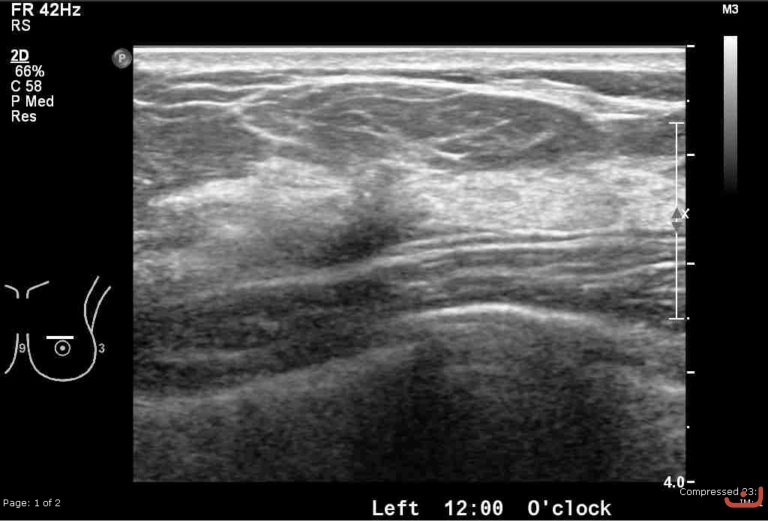

Malignant solid mass

Thursday, 30 April 2015